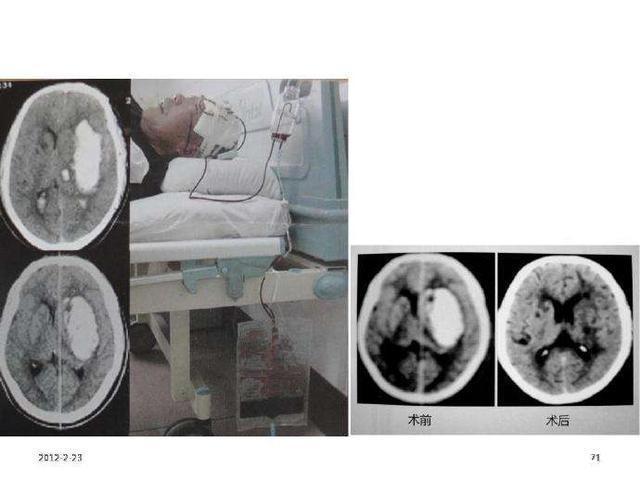

治疗原则为安静卧床、脱水降颅压、调整血压、防止继续出血、加强护理维持生命功能。防治并发症,以挽救生命,降低死亡率、残疾率,减少复发。1、一般应卧床休息2~4周,保持安静,避免情绪激动和血压升高。严密观察体温、脉搏、呼吸和血压等生命体征,注意瞳孔变化和意识改变。2、保持呼吸道通畅,清理呼吸道分泌物或吸入物。必要时及时行气管插管或切开术;有意识障碍、消化道出血者禁食24~48小时,必要时应排空胃内容物。3、水、电解质平衡和营养,每日入液量可按尿量+500ml计算,如有高热、多汗、呕吐,维持中心静脉压在5~12mmHg水平。4、调整血糖,血糖过高或过低者,应及时纠正,维持血糖水平在6~9mmol/L之间。5、明显头痛、过度烦躁不安者,可酌情适当给予镇静止痛剂;便秘者可选用缓泻剂。6、降低颅内压,脑出血后脑水肿约在48小时达到高峰,维持3~5天后逐渐消退,可持续2~3周或更长。脑水肿可使颅内压增高,并致脑疝形成,是影响脑出血死亡率及功能恢复的主要因素。7、一般来说,病情危重致颅内压过高出现脑疝,内科保守治疗效果不佳时,应及时进行外科手术治疗。8、康复治疗,脑出血后,只要患者的生命体征平稳、病情不再进展,宜尽早进行康复治疗。早期分阶段综合康复治疗对恢复患者的神经功能,提高生活质量有益。>脑出血怎么预防?